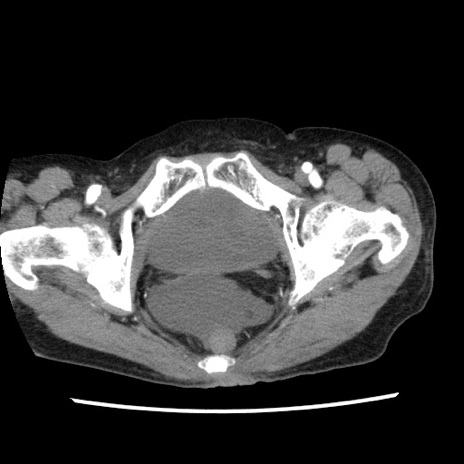

矢状断像

【症例】80歳代女性

【主訴】腹痛

【現病歴】8時間前から腹痛あり来院。

【既往歴】糖尿病、脂質異常症、子宮体癌にて子宮全摘術

【身体所見】意識清明・会話良好だが腹痛で苦悶様、全腹部にわたって反跳痛と圧痛あり

【データ】WBC 13600、CRP 0.14、LDH 224、CK 90